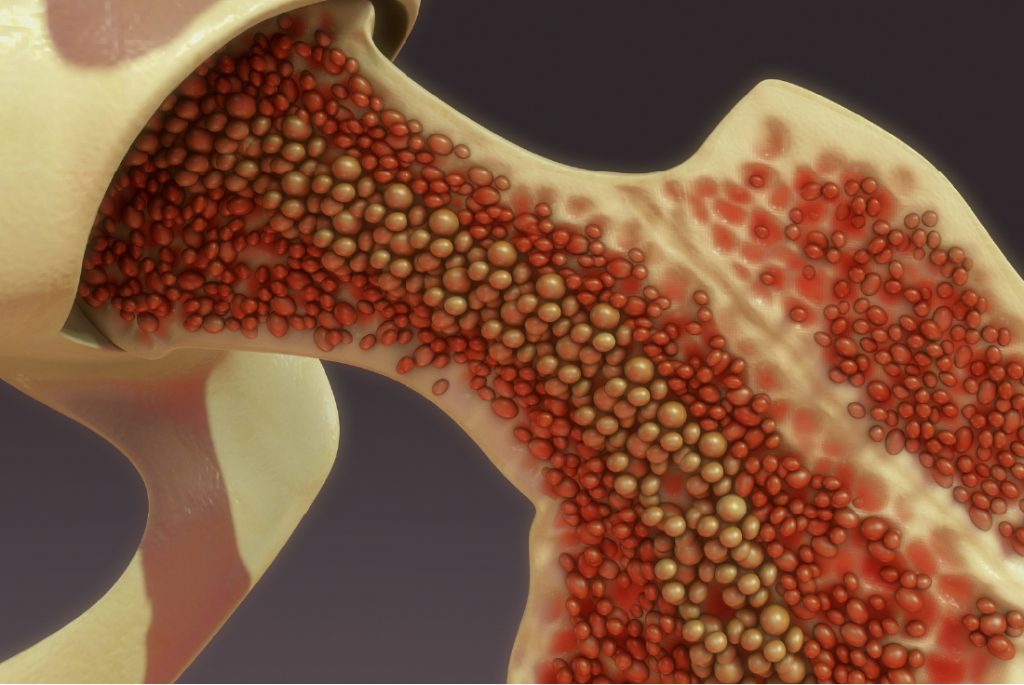

La médula ósea es el tejido esponjoso que se encuentra en el interior de los huesos y desempeña un papel crucial en la producción de diferentes tipos de células sanguíneas, incluidos los eritrocitos (glóbulos rojos), los leucocitos (glóbulos blancos) y las plaquetas. A lo largo de la vida, la médula ósea pasa por cambios significativos en términos de su composición y su capacidad para producir células sanguíneas.

En la infancia temprana hasta los 5 años de edad, la médula ósea de casi todos los huesos es activamente hematopoyética, lo que significa que está involucrada en la producción de una gran cantidad de células sanguíneas, incluyendo eritrocitos. Durante esta etapa, el cuerpo está en rápido crecimiento y desarrollo, y requiere una mayor cantidad de células sanguíneas para satisfacer las necesidades metabólicas y de oxigenación. La médula ósea es rica en células madre hematopoyéticas, que son células madre multipotentes capaces de diferenciarse en diferentes tipos de células sanguíneas.

Sin embargo, a medida que una persona envejece y alcanza la edad adulta, la demanda de células sanguíneas disminuye y el cuerpo tiende a mantener un equilibrio más estable en la producción de estas células. Esto se refleja en cambios en la médula ósea. En particular, las médulas de los huesos largos, como el fémur y el hueso de la pierna, tienden a acumular tejido adiposo (grasa) en lugar de células hematopoyéticas. Las porciones proximales de los húmeros y las tibias, que mencionaste, son excepciones porque tienden a retener cierta capacidad hematopoyética incluso en la edad adulta.

Este cambio en la composición de la médula ósea se debe a una combinación de factores, incluida la disminución de la necesidad de una producción excesiva de células sanguíneas y la redistribución de la función hematopoyética en el cuerpo. A medida que envejecemos, la médula ósea en los huesos largos tiende a ser reemplazada en gran parte por tejido graso, un proceso conocido como «grasa amarilla». La médula ósea en los huesos planos y en las vértebras también puede experimentar este cambio hacia una mayor proporción de tejido graso.